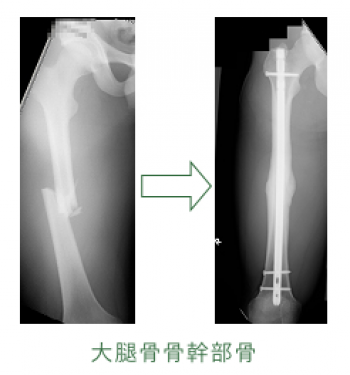

今日、ご紹介するのは、大腿骨骨幹部骨折についてご紹介していきます。

大腿骨骨幹部骨折

大腿骨骨幹部骨折は、比較的頻度が高い。

20~50歳の青壮年に多発するが小児もまれではない。

骨幹部骨折は常に強力な外力により発生するため軟部組織損傷も高度で、開放性骨折になりやすい。